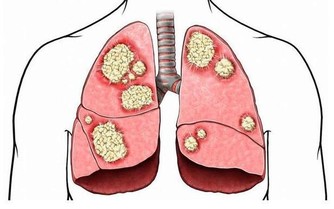

7、身邊有個大菸鬼

統計表明,美國每年有3000名非吸菸人員死於肺癌,30萬兒童患呼吸道感染,二手菸對健康的影響毋須多言。